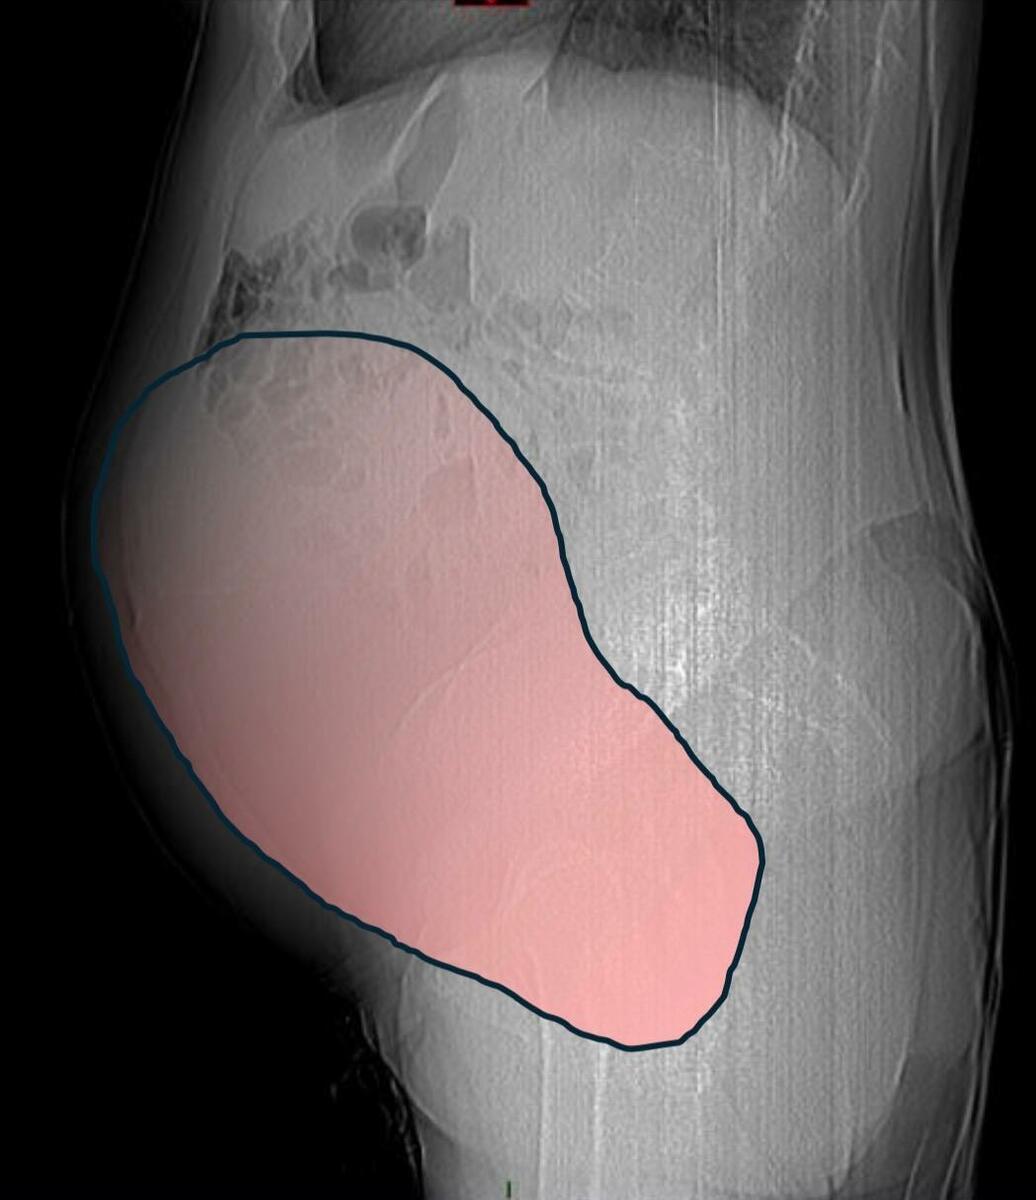

Per mesi la gigantesca cisti ovarica, con un diametro di circa 28 centimetri, è rimasta nascosta, senza dare segnali evidenti. La paziente non si era accorta di nulla. L’allarme è scattato quando la massa, associata alla presenza di una seconda neoplasia intestinale, ha iniziato a comprimere il colon, provocando sintomi acuti ed improvvisi fino a una grave difficoltà intestinale non più ignorabile.

Fondamentale in questa fase il contributo della Radiologia dell'ospedale Sant’Anna, che fornisce l’imaging preoperatorio indispensabile per affrontare un quadro clinico di eccezionale complessità.

Durante l’intervento emerge tutta la gravità della situazione. La gigantesca neoplasia ovarica viene asportata: pesa circa 6 chilogrammi, con un volume paragonabile a quello di una gravidanza gemellare a termine. Ma non è l’unica minaccia. I sintomi più pericolosi sono legati alla sofferenza intestinale, che richiede un intervento immediato e coordinato di più specialisti.